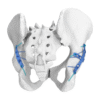

Descripción

Característica :

– El diseño curvo asegura una compresión efectiva del borde de fractura.

– El borde afilado permite la compresión directa del hueso a través de la cápsula articular.

– El primer orificio está diseñado como un orificio alargado, conveniente para elegir la posición del tornillo.

Indicación :

– Fracturas de la pared posterior del acetábulo.